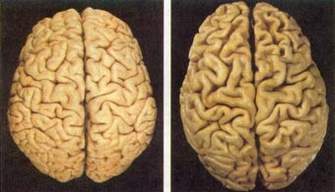

脑扫描诊断老年痴呆症新方法(图)

美国加利福尼亚大学科学家发明一种脑扫描检查新方法,新方法能使医生在患者出现可怕症状之前及时诊断老年弱智或老年痴呆症。

以乔治·巴里奥博士为首的科学家小组研制成一种物质,它能将大脑中淀粉斑与神经原纤维球结合在一起,而大脑中淀粉斑和神经原纤维球是产生老年痴呆症的标志,正是它们引起老年痴呆症患者的智力进行性下降。在实验过程中给9名老年痴呆症患者和7名作为对照的健康者注射一种名为FDDNP的药物,随后给这些人作正电子放射层析X摄影,扫描检查表明,老年痴呆症患者大脑中的淀粉斑和神经原纤维球主要集中在负责记忆的大脑皮层区域。在其中一名患者死亡后还对他的大脑作了仔细研究,研究结果表明,他活着时拍摄的受损大脑照片与死后大脑中淀粉斑和神经原纤维球的实际分布相吻合。